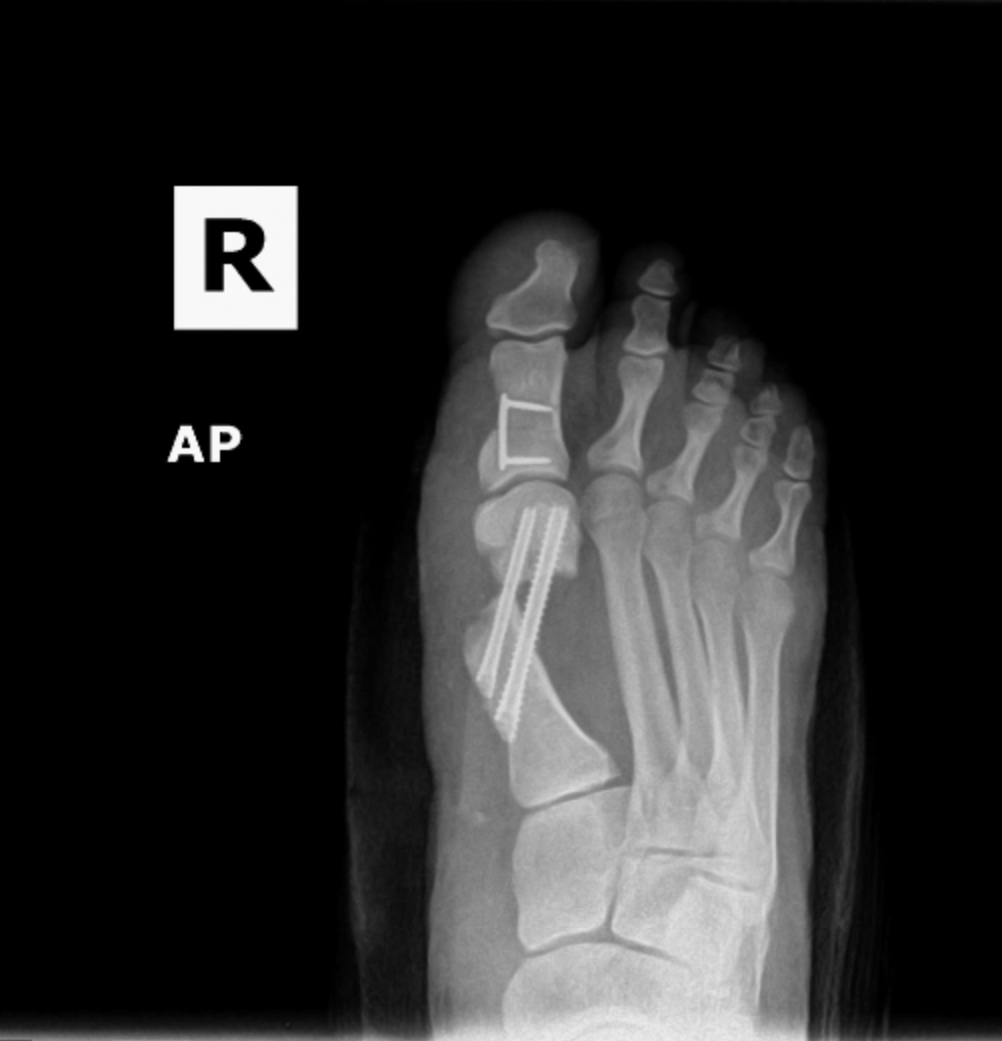

MIS Bunion

MIS3

MIS2